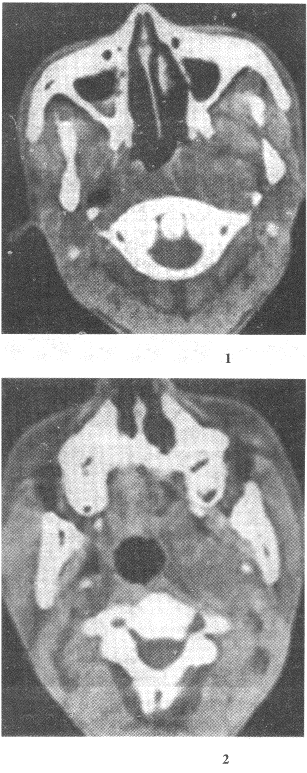

13.女性,43歲。左側(cè)面部不適感1年。CT圖像如圖所示,需要進行鑒別診斷的疾病包括

正確答案:AD 解題思路:膽脂瘤為起源于外胚層的先天性腫瘤,是胚胎早期神經(jīng)溝封閉時,皮膚外胚層的剩件留下來發(fā)展而成。